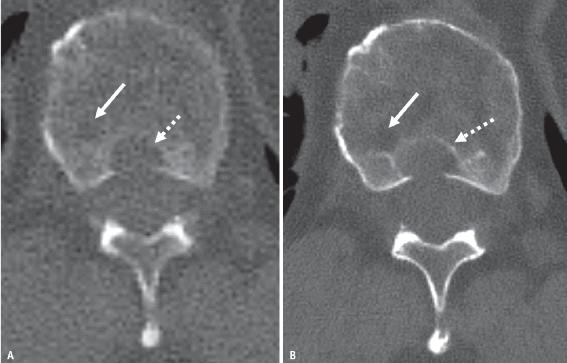

PCD相对于EID固有的更高空间分辨率也有利于低剂量骨骼肌肉CT成像。例如,在多发性骨髓瘤的检查过程中,经常进行低剂量CT扫描,以识别溶解性骨病变和骨髓瘤后遗症,如病理性骨折。在类似的扫描剂量水平下,可以使用超高分辨率模式获取PCD-CT图像。超高分辨率要求在常规CT成像中使用梳状滤波器,这会增加辐射剂量,因此常规EID无法进行低剂量、高分辨率全身CT。在全身低剂量PCD-CT中,在PCD-CT图像上可以更清楚地看到小溶骨性病变(骨髓瘤的特征)(图3)。PCD-CT较小的探测器像素尺寸和较高的几何剂量效率有助于大幅降低小关节超高分辨率成像的辐射剂量,这有利于创伤和退行性疾病。它还允许对肩部和臀部等大关节进行超高空间分辨率成像,这在大多数常规CT系统中不能实现。

图3 56岁男性,患有多发性骨髓瘤。

A、B 通过胸椎的轴位能量积分探测器CT(A)和PCD-CT(B)切片。在PCD-CT图像上可以更清楚地看到胸椎溶解性病变。椎体后部的溶解性病变(后皮质破裂)更清晰(虚线箭头)。在PCD-CT图像上,椎体中较小的溶解性病变(箭头)更为明显。